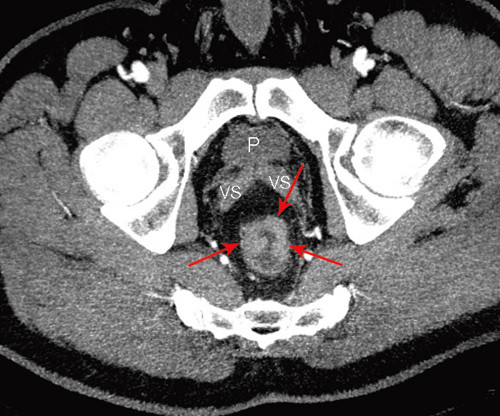

Bruk av CT i utredningen av fjernmetastaser ved kolorektal kreft er en godt etablert metode. CT-undersøkelsens rolle i den lokoregionale utredningen av rectumcancer er betydelig mer usikker. Studier fra de senere år har vist relativt dårlige resultater når det gjelder evaluering av perirektal tumorspredning, med en nøyaktighet på 52 – 74 % (6, 7, 12). Med MDCT-maskiner med minst 16 kanaler har man fått muligheten til å ta tynne bildesnitt som kan rekonstrueres i alle plan med samme gode bildekvalitet (fig 1, fig 2). Slik kan man få bilder parallelt og perpendikulært til tumors lengdeakse, analogt til MR-undersøkelsen. Det er vist at bruken av slike rekonstruerte bilder signifikant bedrer evalueringen med multidetektor-CT (13). Det finnes få studier der man har sammenliknet MDCT-undersøkelse med andre metoder ved rectumcancer, men resultatene så langt synes å være lovende (14) – (17).

Man venter snart resultater fra en ny, stor multisenterstudie i Nederland der bruk av CT-undersøkelse ved rectumcancer evalueres. I en nyere artikkel av Beets-Tan og medarbeidere refereres det til preliminære resultater som viser at MDCT er likeverdig med MR i øvre/midtre del av rectum, mens MR er overlegen i nedre del (18). I forhold til MR har CT dårligere evne til å skille bløtdelssjiktene fra hverandre i dette området, hvor subtile detaljer som 1 – 2 mm infiltrasjon kan skille en T2-tumor fra en T4-tumor (fig 3).